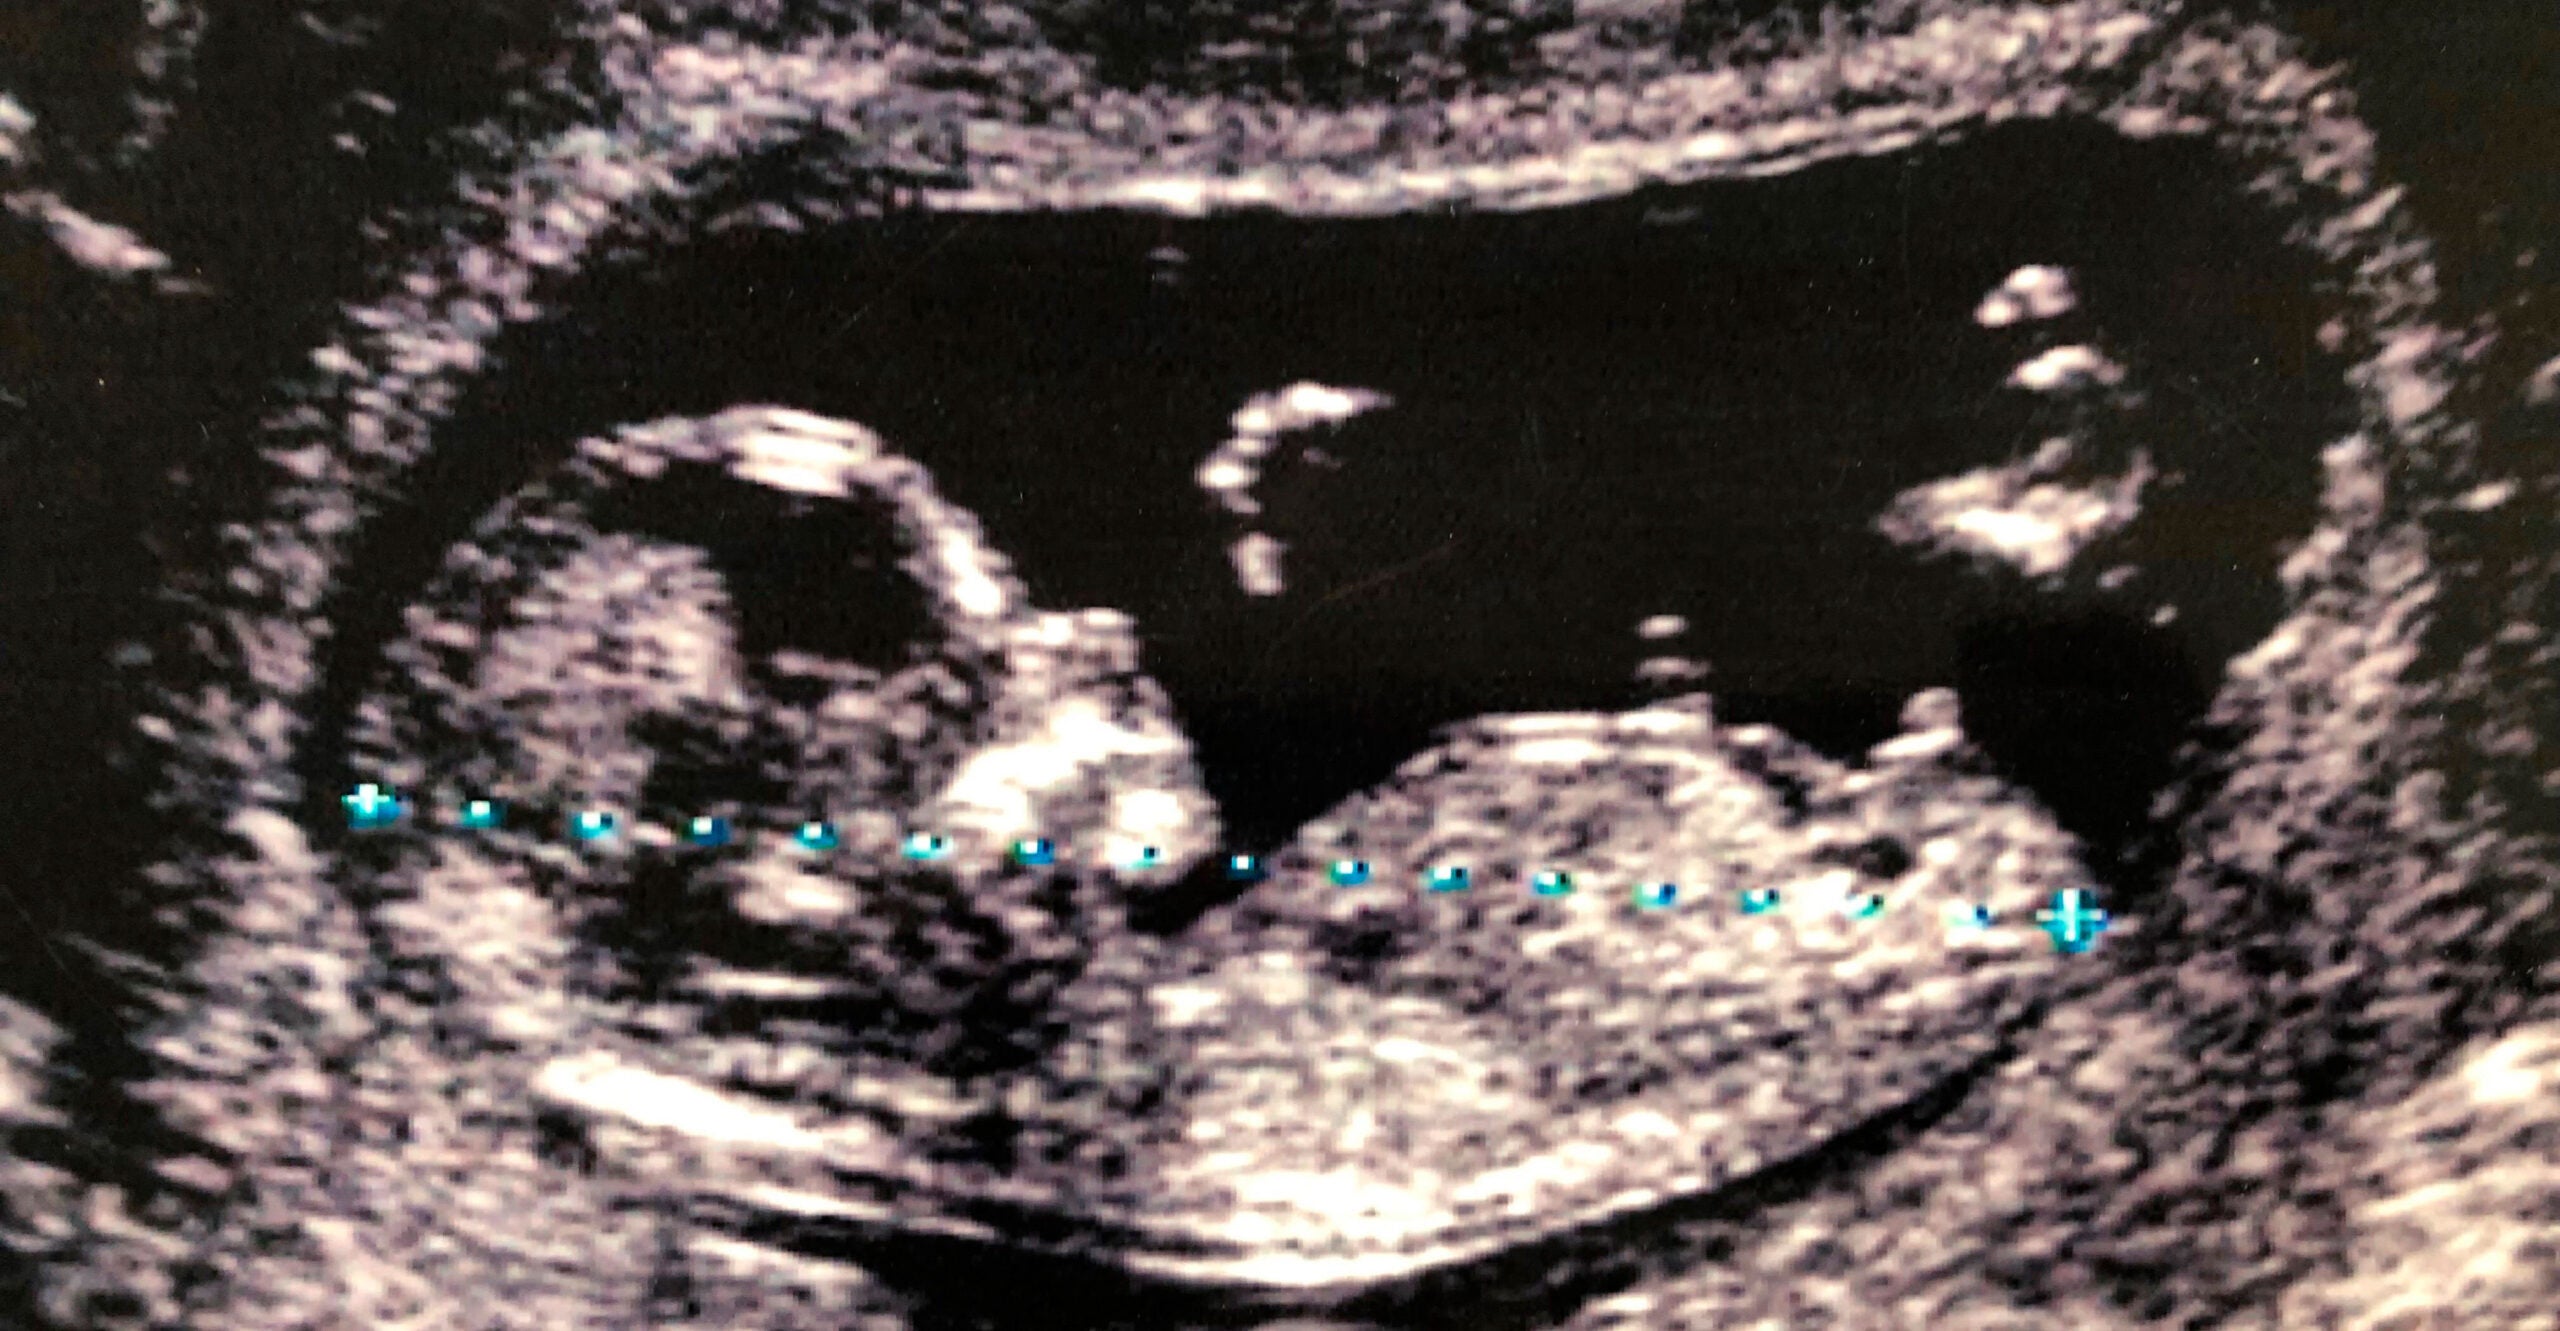

False Positives for Genetic Disorders in Prenatal Testing Unacceptably High

By Tara Sander Lee

Positive results on prenatal genetic screenings can be wrong up to 85% of the time, and yet hundreds of thousands of those tests are performed annually.